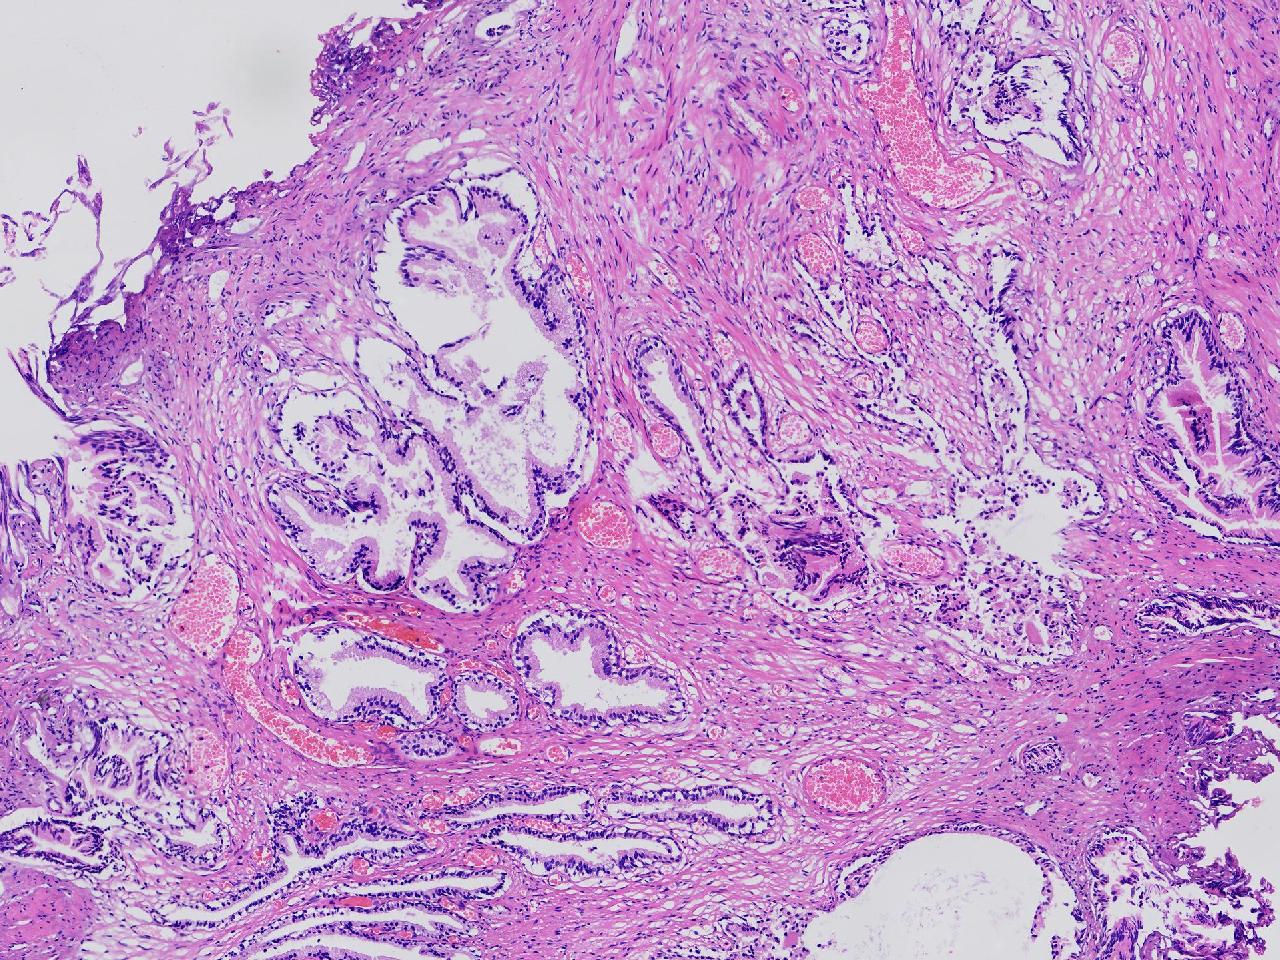

良性前列腺增生?

男,68岁,排尿困难半年余。行前列腺前切术。

前列腺电切标本

灰粉色条索状软组织多块,4X3X3厘米。

考虑为良性前列腺增生症

良性增生

BPH.